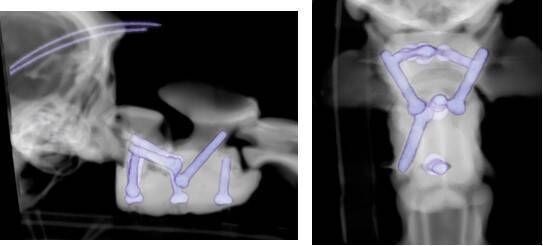

It was recommended that Arthur be taken to Chestergates Veterinary Hospital in Chester. Here one of the Britain's leading teams of veterinary neurologists conducted MRI scans and X-rays of his spine to see if they could identify the problem.

They established that a section of Arthur's spine was not properly connected together which had been caused by instability of his first and second cervical vertebrae. This was compressing his spinal cord severely, causing loss of function in all four of his limbs.

To treat Arthur, a team of specialist veterinary surgeons at Chestergates joined forces with Fusion Implants in Liverpool to create bespoke 3D-printed spinal screws and special surgical cement to help stabilise his spine.

One week later, Arthur was taken into surgery. Here a team specialist veterinary surgeons and nurses undertook a precise four-hour operation to carefully place the new 3D-printed section into Arthur's spine.